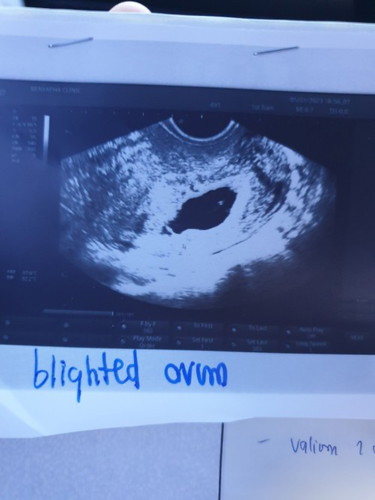

ประสบการณท้องที่สาม ท้องลม อายุครรภ์ประมาณ2เดือนกว่า ซาวน์3รอบเจอถุงครรภ์ ไม่เจอถุงไข่แดง ไม่เจอตัวอ่อน หมอให้สองทางเลือก 1.ใช้วิธีการดูดและขูดมดลูก 2.รอร่างกายขับออกเอง(แต่จะทรมานและเสี่ยงตกเลือด) แม่เลือกวิธีที่1.ตัดสินใจแอดมิด 6/1/66 ได้กลับบ้านวันนั้นเลยตอน2ทุ่มครึ่ง หมอแนะนำให้พักร่างกาย1เดือน แล้วเริ่มใหม่ ท้องต่อไปโอกาสท้องสมบูรณ์สูงมากๆ #แชร์ประสบการณ์ #ท้องลมครั้งที่2 #ท้องแรกท้องลมแท้งเองแบบสมบูรณ์ทรมานสุดๆ #ท้องสองน้องฟ้าใสได้2ขวบกว่าแต่ไม่ค่อยแข็งแรง